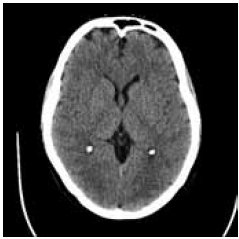

Paciente de 58 anos é admitido na unidade de emergência apresentando rebaixamento do nível de consciência, evoluindo para coma nas últimas horas. Não há histórico médico de abuso de drogas e nem de etilismo, e a família relata que ele estava bem até dois dias atrás. Ao exame físico, o paciente não responde a estímulos verbais ou dolorosos e apresenta respiração irregular do tipo Cheyne-Stokes, pupilas médio-fixas e pouco reagentes à luz. A tomografia computadorizada (TC) de crânio sem contraste encontra-se a seguir.

(https://prod-images-static.radiopaedia.org/ images/4170261/c5d7c3ed6c7fe53e59c2dd902e44b9_big_gallery.jpg)

Com base nesse cenário clínico e nos conhecimentos sobre as etiologias e os mecanismos fisiopatológicos associados ao coma, das seguintes alternativas, assinale a que apresenta a mais provável causa do estado comatoso desse paciente.